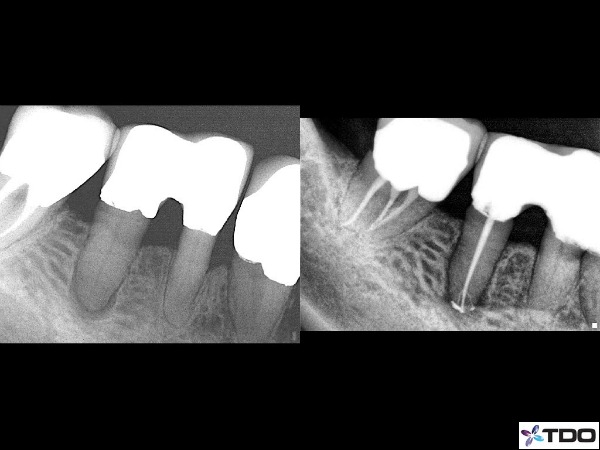

Case 2: Bicuspid with apical anatomy captured

There are very subtle twists and turns throughout a canal system. If we are not careful a ledge or block is easy to create especially in the last few millimeters of a canal system. Placing a small bend on a hand file can be very helpful to capture that elusive apical anatomy that can be so crucial to the success of a case. The small bend can also help slip into a canal system that splits from one main canal into two.